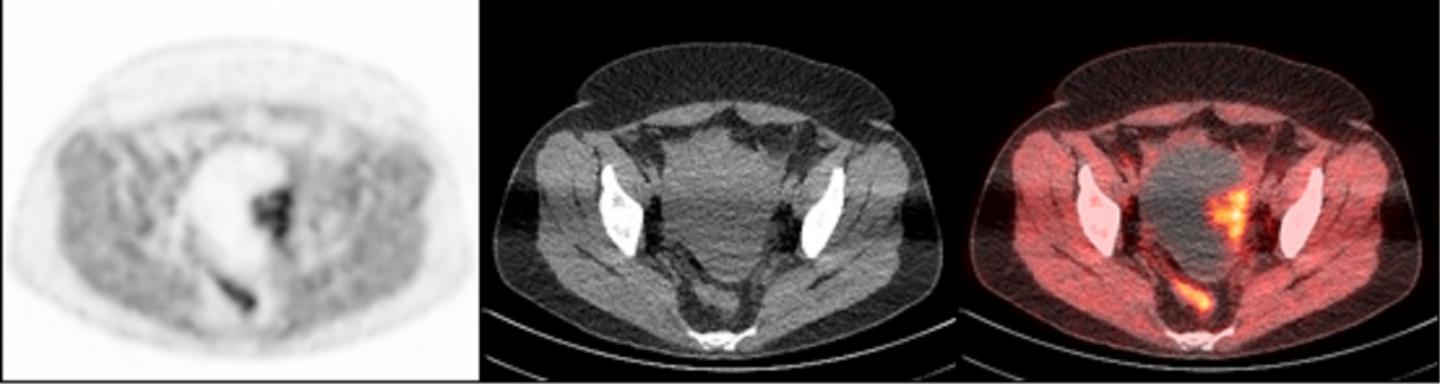

To accomplish this, researchers used a radioactive tracer that binds to PARP-1, making it visible during PET scans. The tracer, called FluorThanatrace, was specially designed by Robert H. Mach, PhD, the Britton Chance Professor of Radiology. After a pre-clinical test using mouse models showed the tracer was hitting its specific molecular target, the study's authors moved to a phase I trial.

A clinical trial involving 10 patients led to 13 tissue samples. These samples had a wide spectrum of uptake of the tracer, but that uptake correlated with PARP-1 expression. In other words, the more the tracer was able to bind to the tumor, the higher the level of PARP-1 that tumor expressed.

"This is proof-of-concept that we not only have a potential biomarker for the effectiveness of PARP inhibitors, but we also have a non-invasive imaging technique to find that biomarker in ovarian cancer patients," Makvandi said.